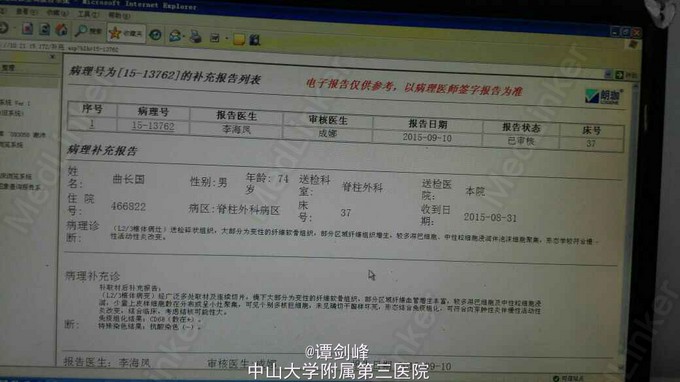

脊柱结核(L2、L3)

男性,74岁高龄患者,因腰痛2年余入院。无低热、乏力、盗汗等典型结核症状,既往腰椎X片提示有椎间盘病变,容易误诊成腰椎间盘突出症,漏诊脊柱结核。后来我院就诊,腰椎MR提示:腰椎结核。行手术治疗,术后病理证实为脊柱结核,术后患者腰痛基本缓解,复查腰椎MR未见明显异常。继续予四联抗结核治疗,CRP及血沉基本降至正常后出院。出院后继续抗结核治疗,1月后返院复查。